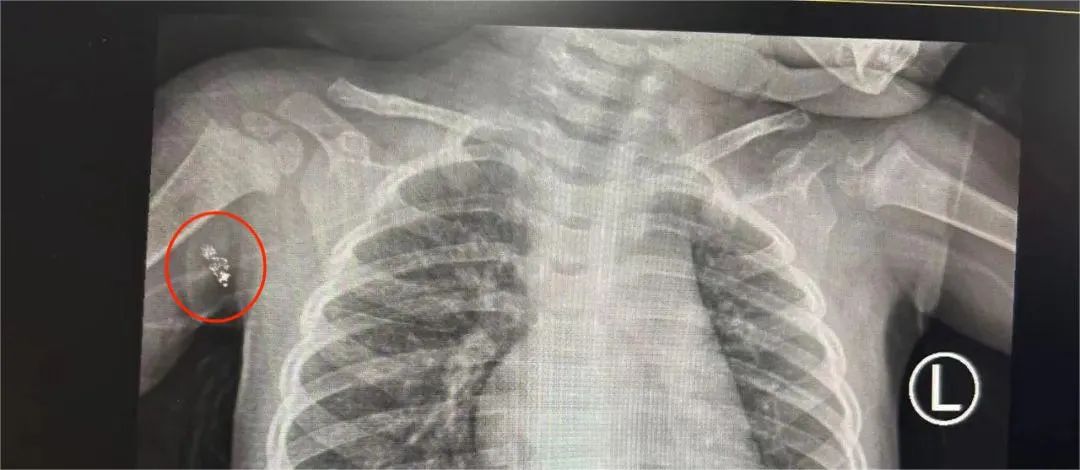

*6 mm,结合 CT 等检查基本可明确躯干浅表异物是水银在皮下残留,有手术指征,应尽早行手术治疗。

日间手术中心副主任徐维立即为 瑾瑾 进行手术治疗,术中见水银残端位于皮下软组织深部,紧贴腋下大血管及腋神经,周围可见淋巴结明显肿大,在手术团队的精湛操作下,顺利取出异物,术后拍片检查,确认异物已完全清除。